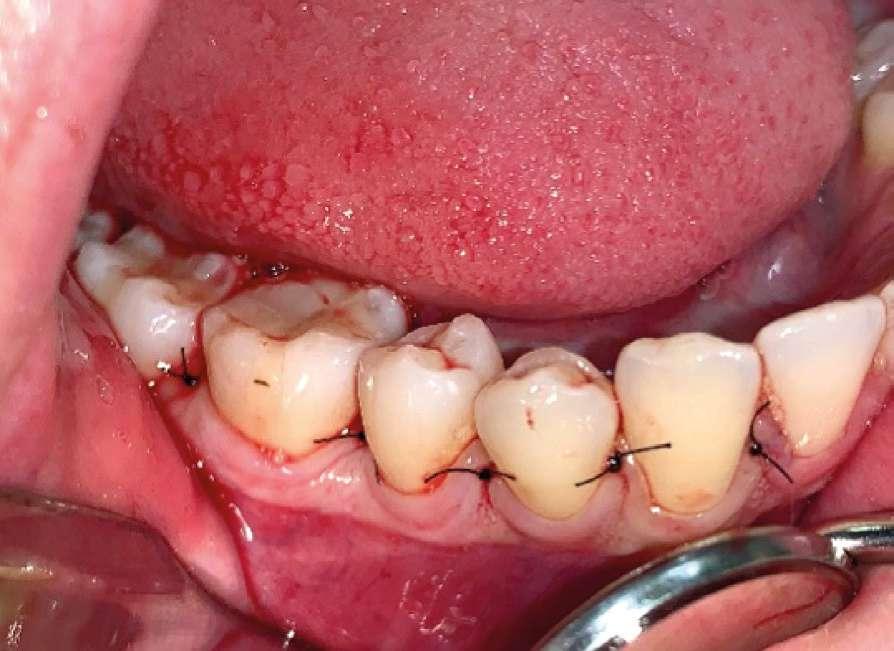

Una vez finalizada la intervención se procedió a realizar sutura interpapilar con sutura monofilamento 5/0 (Fig. 7 y 8).

A la paciente se le prescribió una pauta antibiótica postoperatoria de Amoxcilina 500 mg 1/8h durante 5 días, sumada al uso de Ibuprofeno 600 mg con Paracetamol 1g como analgésico de rescate. Fueron pautados enjuagues con clorhexidina 0,2% a partir de las 24 horas de la intervención, revisando la zona a la semana, momento en que se retiró la sutura y se pudo comprobar que la paciente no presentaba ninguna alteración sensitiva en la zona (Fig. 9).

Figuras 7 y 8. Zona quirúrgica suturada desde una visión oclusal y vestibular.

Figura 9. Revisión a la semana de la cirugía.